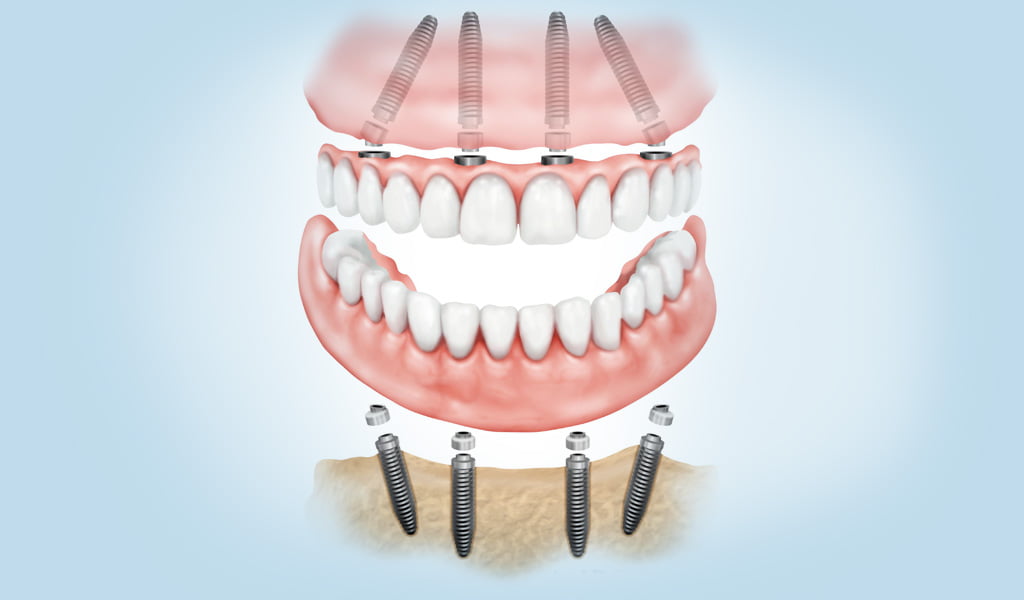

Boca completa en 1 dia

És la tècnica implantológica de càrrega immediata. Es realitzarà l’extracció de les peces danyades (en el cas que existeixin), a continuació s’insereixen els implants i col·loquem les dents noves. El pacient acaba el seu tractament i surt de la clínica amb les seves dents provisionals “fixos” col·locats en el mateix dia.

Per a poder realitzar aquest tractament en 1 sol dia, és necessari que el pacient es realitzi un TAC 3D prèviament, ja que aquesta informació s’usarà en el programari per a guiar la la cirurgia i crear les pròtesis dentals a mesura.